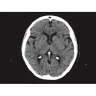

Области применения

Позволяет проводить комплексные исследования всех анатомических зон, включая нейровизуализацию, ангиографию, исследования органов грудной и брюшной полости. Особенно эффективен для раннего выявления онкологических заболеваний.

Обеспечивает высокую точность при кардиологических исследованиях, визуализации костных структур и суставов. Подходит для динамического наблюдения в ходе лечения.